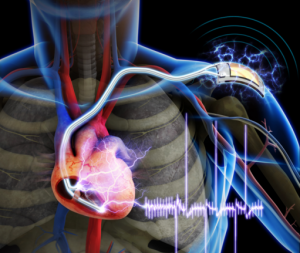

Son yıllarda kardiyak pili yani kalp pili teknolojisi oldukça gelişti. Son yıllarda gittikçe yaygınlaşan pacemaker ;(kapl pili) teknolojisi sayesinde milyonlarca kişinin hayatı kurtuluyor.

Her şeye rağmen bu cihazlar pille çalıştığından her 7 yılda bir değiştirilmesi gerekiyor. İşte KAIST’den (Kor e Bilim ve Teknoloji Enstitüsü) bilim adamları vücuttaki kaslardan elektrik üreterek vücutta uzun süreli kalabilecek bir implant geliştirdiler. KAIST araştırma ekibinden Prof. Keon Jae Lee ve Prof. Doktor Boyoung Joungesnek esnek bir piezoelektrik nanojeneratör geliştirerek bir fareye taktı. Bu kadar küçük bir bedende çalışabilen esnek düzenek gerçekten işe yarıyor.

Sonuç olarak yeni cihaz 8.2 volt ve 0.22mA elektrik enerjisi üreterek nanojeneratörler sayesinde ufak kas hareketlerini bile enerjiye çevirebiliyor. Elde edilen voltaj farenin kalbini doğrudan çalıştırmaya yetiyor. Bu kendi kendine enerji üreten nano jeneratörler sayesinde kardiyak pacemakerların ömrü arttırılarak pil değiştirme ameliyatları azaltılabilir. Hatta bu sayede görüntüleme implantlarına da enerji sağlanabilir. Bu sayede kalp krizleri engellenerek gerçek zamanlı kardiyak aritmi teşhisi yapılabilir.

Daha öncesinde kalbinde atması enerji sağlamaya yarayan diğer teknolojiler, örneğin ışık kontrollü non-viral optogenetikler gibi dış kaynaklar üzerinde çalışmalar sürerken, piezoelektrik jeneratörler buna öncülük edebilir.